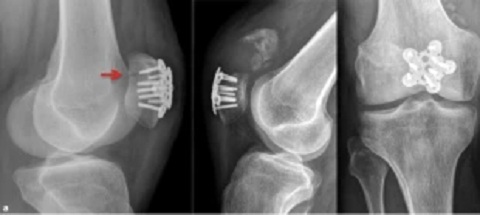

Hier haben wir Röntgenfotos mit den Schrauben bei einem einfachen Bruch der Kniescheibe: die Frontansicht (1'48'') und die Seitenansicht (1'52'') [web02].

Manchmal kommen auch Metallplatten zum Einsatz:

Kniescheiben-OP mit eingeschraubten

Platten   Kniescheiben-OP mit eingeschraubten Platten,

Röntgenfotos frontal und lateral

Kniescheiben-OP mit eingeschraubten Platten [17] - Kniescheiben-OP mit eingeschraubten Platten, Röntgenfotos frontal und lateral [18]